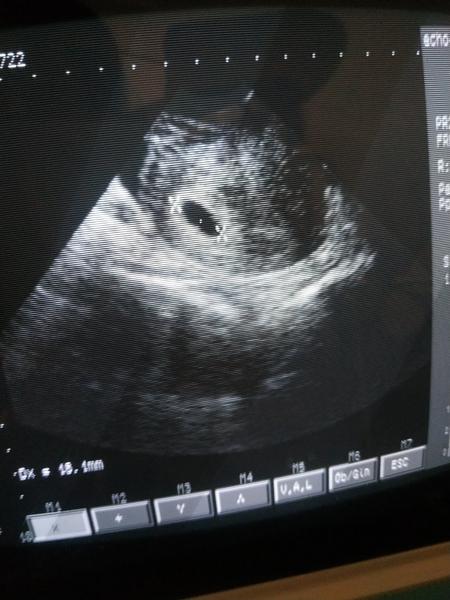

@ivuskake ja som mala v 7tt + 0 veľkosť plodu 0,87 cm a bilo srdiecko

@ivuskake toto je 7+2